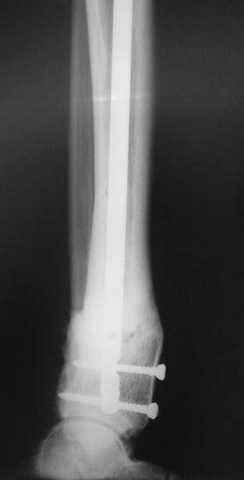

5, 6 - через 2,5 мес после травмы выполнен закрытый остеосинтез блокируемым штифтом.